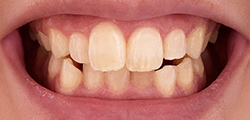

お子さんの顎の成長を利用して

行う矯正治療

小児矯正は、「I期治療」と「II期治療」という二つのステップに分けられます。大人の矯正が「すでに生え揃った歯を動かす」治療であるのに対し、小児矯正はお子さんの顎の成長を利用しながら治療を進められるのが特徴です。お子さんの成長段階や歯ならびの状態に合わせて、I期治療だけで済む場合、II期治療から始める場合、I期・II期を組み合わせて行う場合があります。

I期治療

主に永久歯が生え始める時期に行います。顎の成長を促したり、歯列を広げたりする装置を使い、将来的に永久歯が正しく並ぶためのスペースを確保するのが目的です。

Ⅱ期治療

永久歯が生え揃った後に行う、いわゆる「本格的な矯正治療」です。当院が採用している「マルチブラケット」のように、歯の表面に装置(ブラケット)を取りつけ、ワイヤーを通して歯を一本一本正しい位置へと動かし、美しい歯ならびと正しい噛み合わせを完成させます。

子どもの口腔内は成長に伴って変わっていくため、小児矯正はⅠ期とⅡ期の治療に分けられます。Ⅰ期では歯が並ぶスペースを確保するため顎を広げ、Ⅱ期では歯に力を加えて歯ならびを整える方法を取ります。お子さんの年齢や状態に応じて治療をご提案させていただきます。